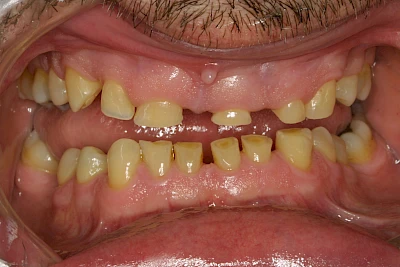

- Abnutzung durch Kauen (Abrasion) oder duch durch übermäßiges Knirschen bzw. Pressen (Attrition)

Die Zähne können dabei auf Reize (warm, kalt, süß, sauer) oder auch beim Zähneputzen empfindlich oder schmerzhaft sein. In allen diesen Fällen ist es sinnvoll, den Zahnarzt zu kontaktieren und das weitere Vorgehen abzustimmen.